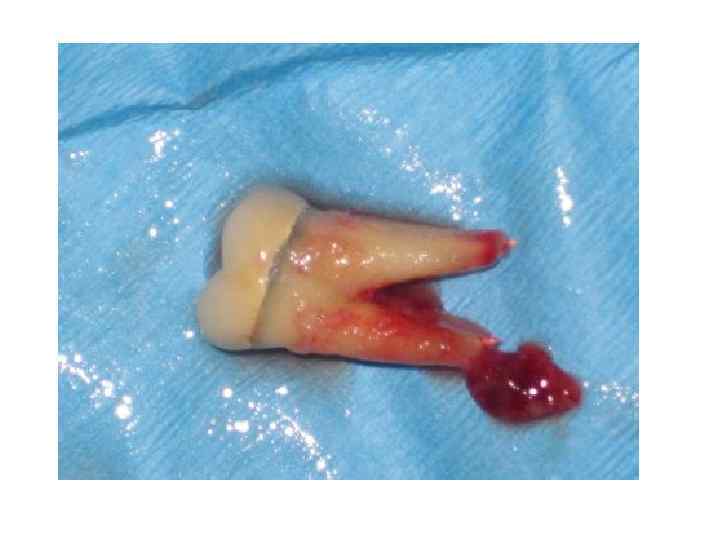

Реплантация зуба Возвращение в лунку удаленного зуба. Операцию проводят при безуспешности или невозможности консервативной терапии, нежелательности удаления зуба. Заключается в удалении зуба, выскабливании патологических тканей из альвеолы и с поверхности корня. После пломбирования каналов и резекции верхушек корней, зуб вводят в лунку и фиксируют там. Производят реплантацию преимущественно многокорневых зубов. Большое значение для успеха реплантации имеет сохранность круговой связки. Зуб удаляют осторожно, стараясь не травмировать тканей зубной альвеолы и прилегающих мягких тканей. Так же осторожно делают кюретаж альвеолы, убирая грануляционные разрастания или гранулему, стараются сохранить волокна периодонта по боковой поверхности альвеолы и круговую связку. Промывают рану теплым изотоническим раствором натрия хлорида с добавлением антибиотиков (грамицидин, линкомицин и др. ) и рыхло тампонируют стерильной марлей. Удаленный зуб временно помещают в какую-либо емкость, содержащую теплый (36, 6 °С) изотонический раствор натрия хлорида с добавлением антибиотиков или раствора хлоргексидина. Пломбируют полость зуба и каналы стеклоиномерным цементом, но лучше МТА цементом , создающим лучший герметизм и не влияющим токсически на костную ткань. Отпиливают верхушки его корней. Иногда корни зубов не резецируют, а только расширяют каналы и осуществляют медикаментозную обработку и их пломбирование. При этих манипуляциях осторожно держат зуб стерильной салфеткой и обязательно помещают его в консервирующий раствор (изотонический раствор натрия хлорида), После туалета кости зуб помещают в альвеолу и фиксируют его при помощи проволочной шины, защитной пластинки из быстротвердеющей пластмассы, проволочно-композитной фиксации, каппы на 2— 3 нед.